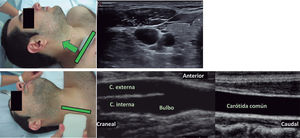

Se recomienda la utilización, como primera línea de estudio, el eco-Doppler y, posteriormente, angio-TC y angio-RM para la estratificación de la estenosis carotídea.

La integración de otros parámetros además de la VPS permitirá estimar con mayor certeza el grado de obstrucción carotídea.